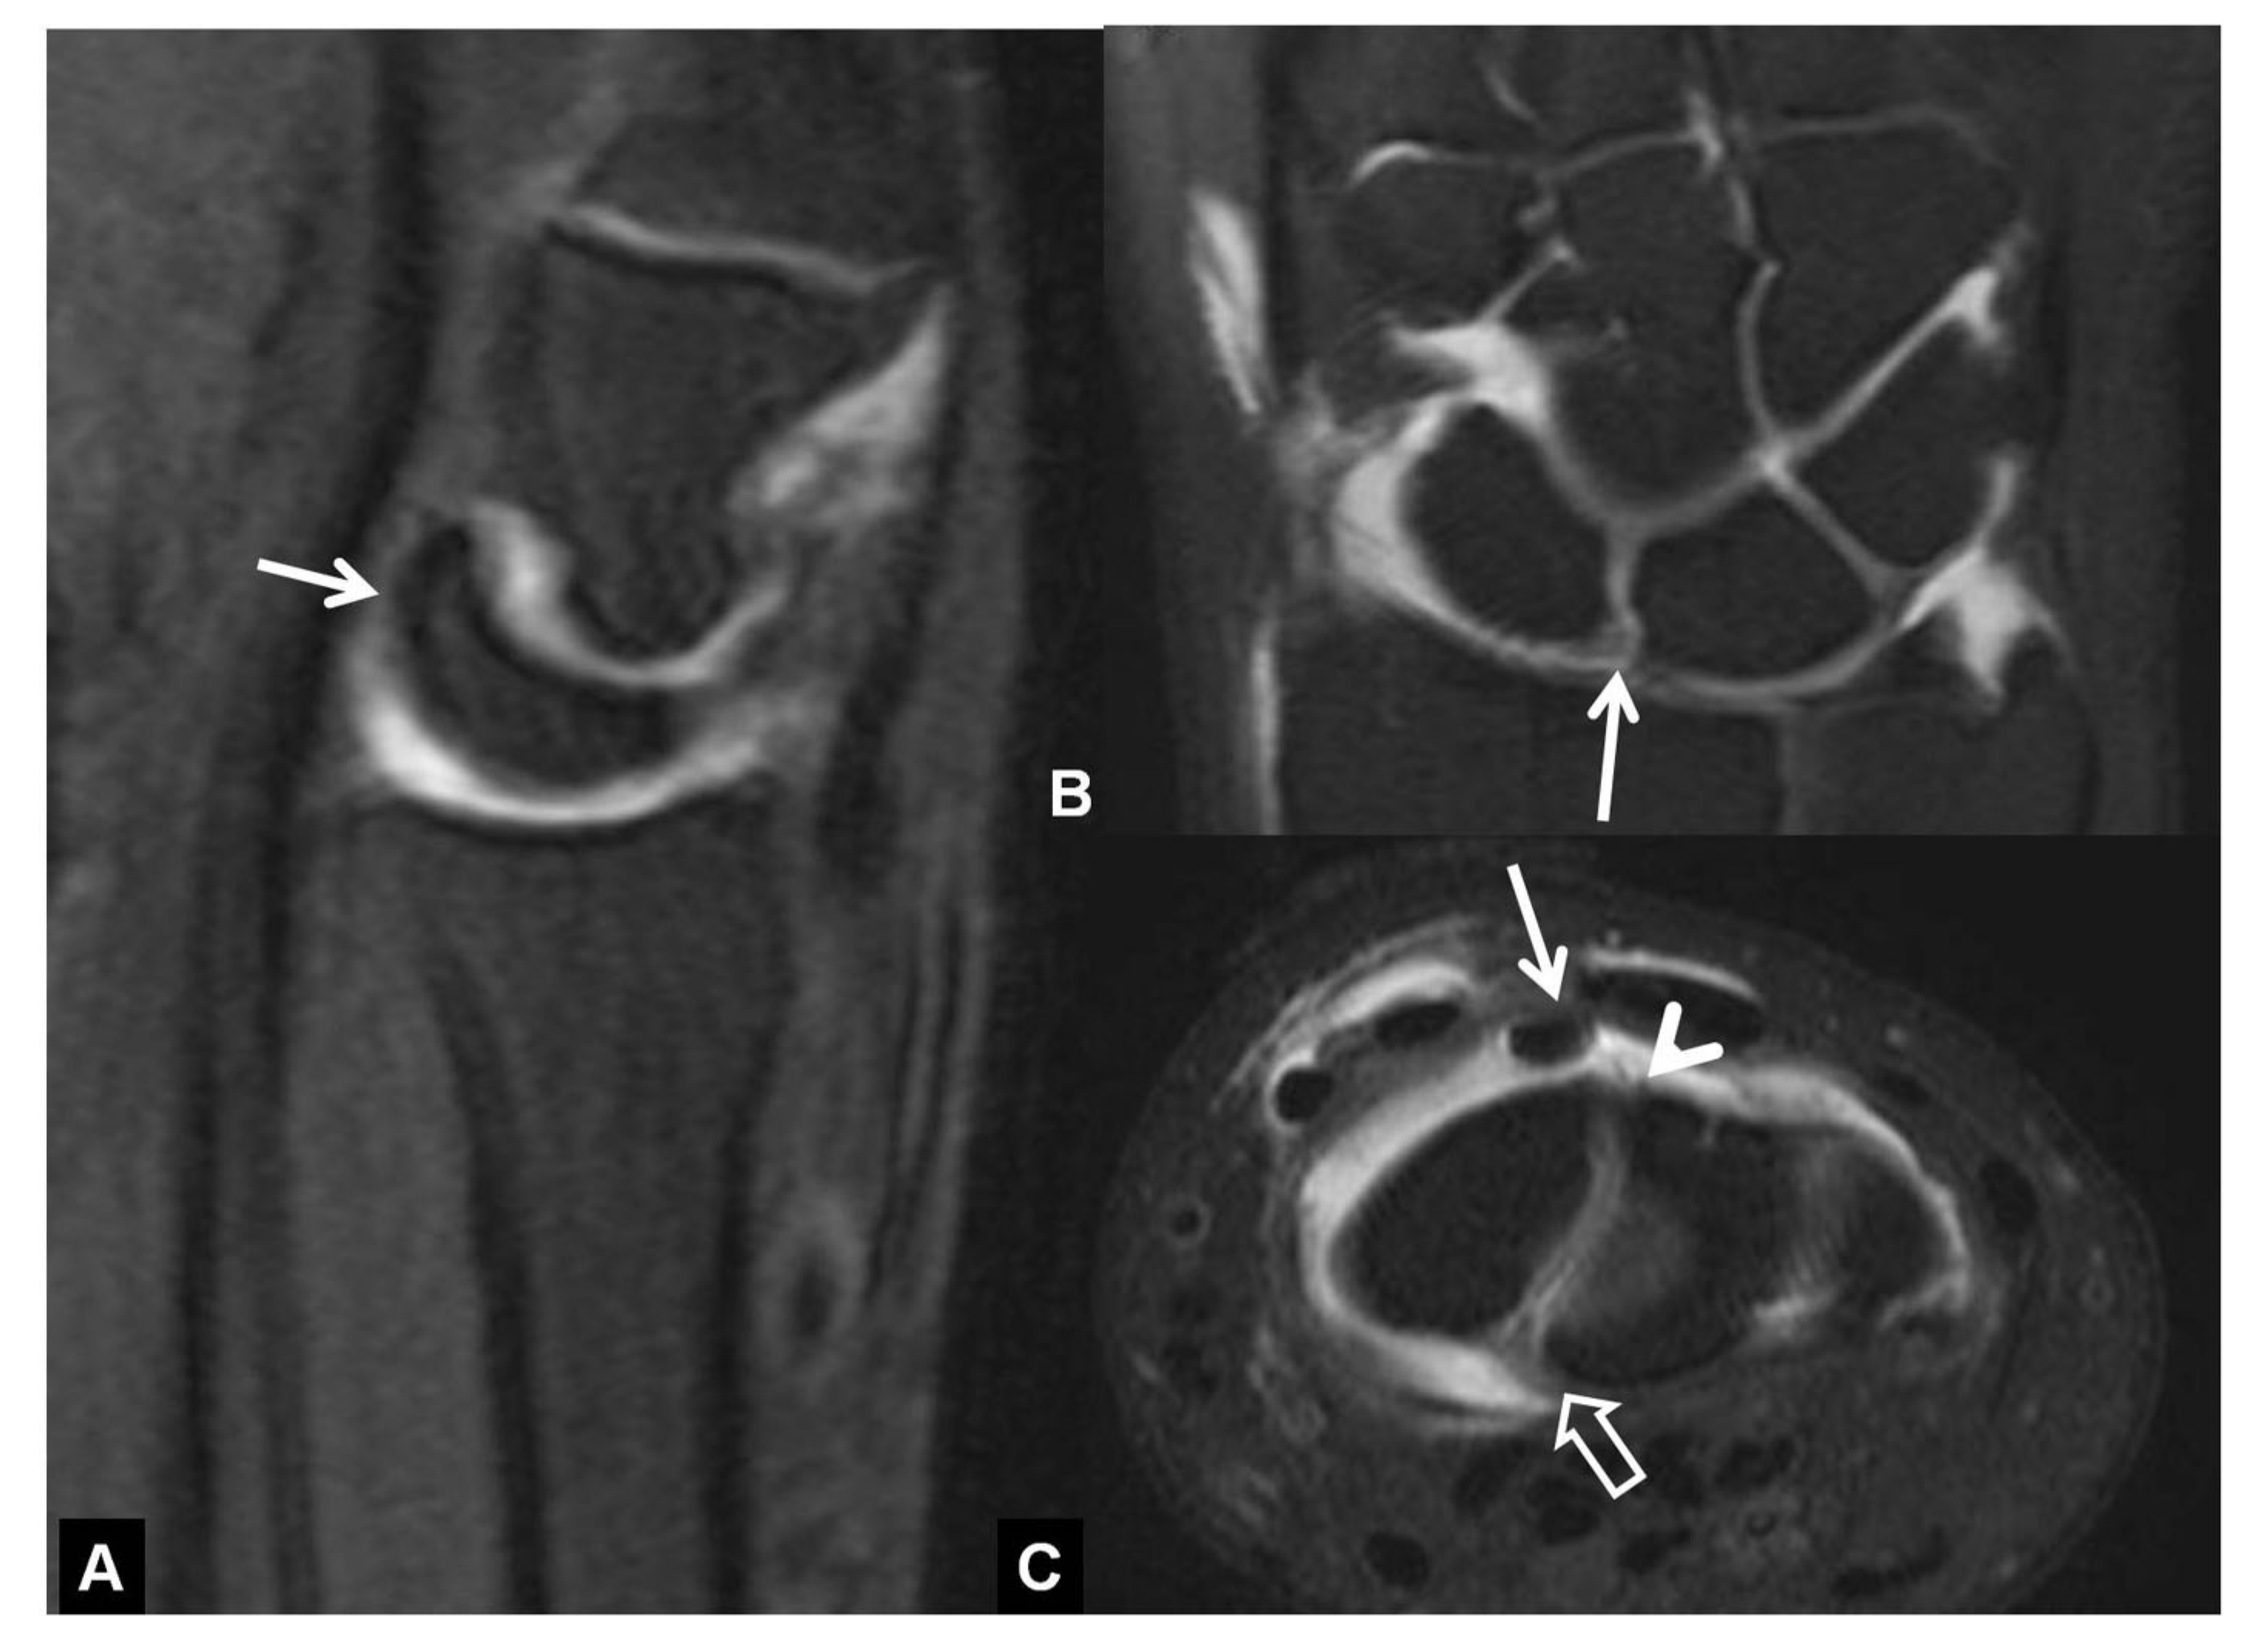

CT-arthrography (CTa) is performed with an iodine contrast material injected in specific wrist joints. For depicting a SLL tear, a single injection at the radioscaphoid joint is performed in our department under fluoroscopic or ultrasound guidance. In the presence of a tear, the midcarpal joints will be opacified (Figure 8).

Figure 8.

A 33-year-old with a history of scaphoid fracture. (A) Coronal CT-arthrographic image showing the scaphoid pseudarthrosis (open arrow), a radial styloid process fracture (arrowhead) and an intact scapholunate ligament (arrow). (B) Axial CT-arthrographic image showing the intact dorsal (arrow) and palmar (open arrow) parts of the scapholunate ligament. A 56-year-old male patient who was involved in a motor vehicle accident 1 year prior to current imaging. Coronal (C) and axial (D) CT-arthrographic images showing a tear at the membranous (arrow) and palmar (open arrow) parts of the scapholunate ligament.

In SLAC, one of the main CTa findings is the partial or complete tear of SLL [9,10]. Axial images are more suitable for the estimation of the volar and dorsal part of SLL, the coronal for the membranous part of SLL and sagittal reconstruction images are appropriate for the evaluation of DISI (Figure 9).